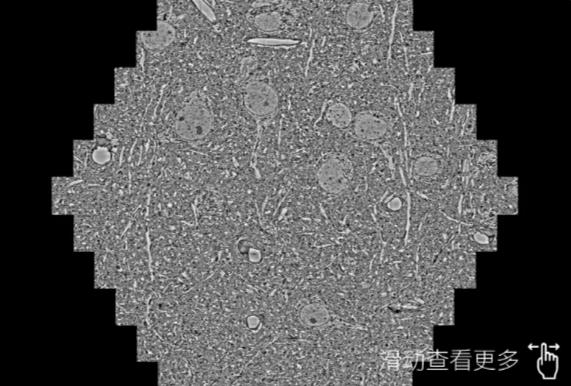

鼠脑切片。左图使用松原蔡司松原扫描电镜MultiSEM706对165μmx143pm面积区域成像,耗时仅需1.5秒。右图为鼠脑切片中30μm区域放大效果。样品由芝加哥大学B.Kasthuri提供。